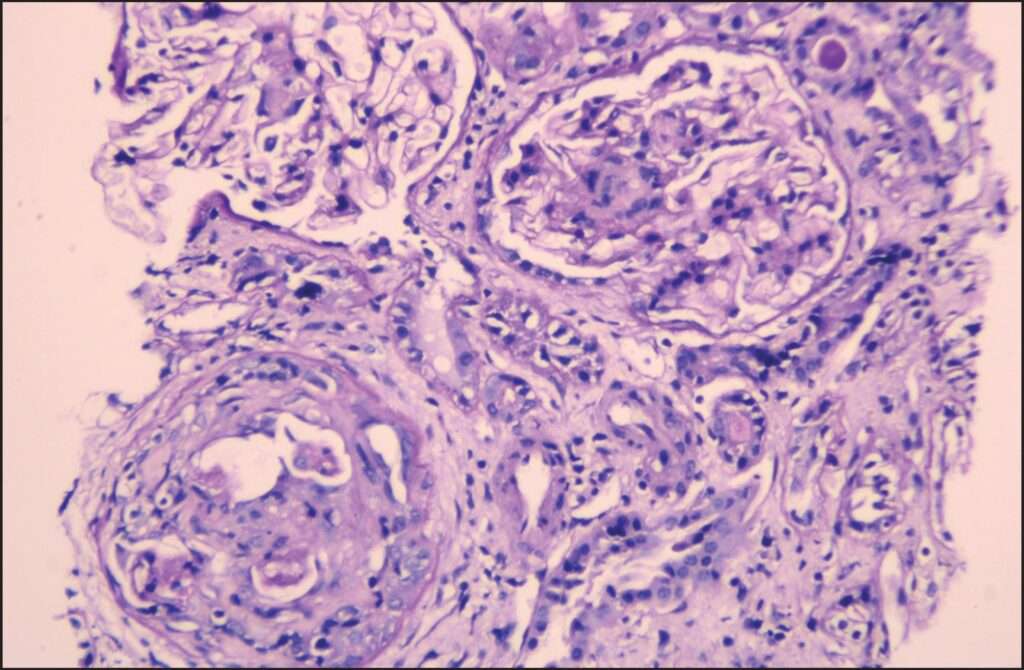

Además de los estudios serológicos, el diagnóstico definitivo de la vasculitis asociada a ANCA generalmente requiere la realización de una biopsia renal, especialmente cuando hay signos de daño renal, como la hematuria y la proteinuria. En la biopsia renal de pacientes con estas condiciones, la microscopía óptica revela lesiones necrotizantes en los glomérulos y la presencia de semilunas, que son formaciones extracelulares que resultan de la proliferación de células parietales y la fuga de proteínas y componentes celulares. Estas semilunas son un hallazgo característico de la glomerulonefritis rápidamente progresiva (RPGN), que se asocia con la vasculitis severa.

A pesar de la presencia de estas lesiones en la biopsia renal, un aspecto distintivo de la glomerulonefritis asociada a ANCA es la falta de depósitos inmunes en el tejido renal. Cuando se realiza una técnica de inmunofluorescencia en la biopsia renal, no se observan depósitos de inmunoglobulinas ni de componentes del sistema del complemento, lo que lleva a la clasificación de la glomerulonefritis como «pauci-inmune». Este hallazgo es fundamental para diferenciar la glomerulonefritis asociada a ANCA de otras formas de glomerulonefritis, como las que se observan en enfermedades autoinmunes sistémicas, como el lupus eritematoso sistémico, donde los depósitos de inmunocomplejos son más prominentes.

El pronóstico a largo plazo, sin embargo, depende en gran medida de la extensión del daño renal antes de iniciar el tratamiento. Los pacientes que presentan una insuficiencia renal avanzada en el momento del diagnóstico, especialmente aquellos con glomerulonefritis rápidamente progresiva, tienen un pronóstico menos favorable. La presencia de semilunas en la biopsia renal, que son un signo de daño glomerular extenso, a menudo se asocia con un curso clínico más grave y una mayor probabilidad de insuficiencia renal crónica. Por lo tanto, la intervención temprana es crucial, ya que el daño renal preexistente tiene un impacto directo en la capacidad de recuperación del paciente.